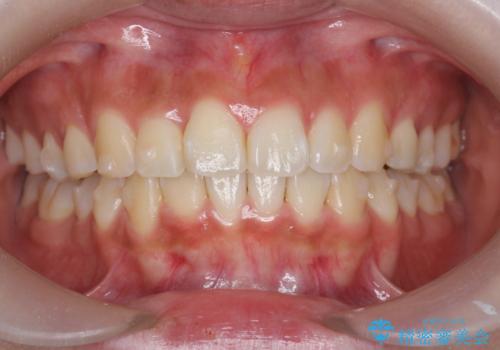

- 前歯の目立つねじれを矯正治療で治したい、と来院されました。

マウスピース矯正を始める前に、ねじれを取るのが短期間で済む部分ワイヤー小矯正を行うことで、全体的な治療期間を短くする治療計画を実行していきます。

前歯のねじれはマウスピース矯正の苦手な動きになり、治療期間が長くなる原因になりやすいです。